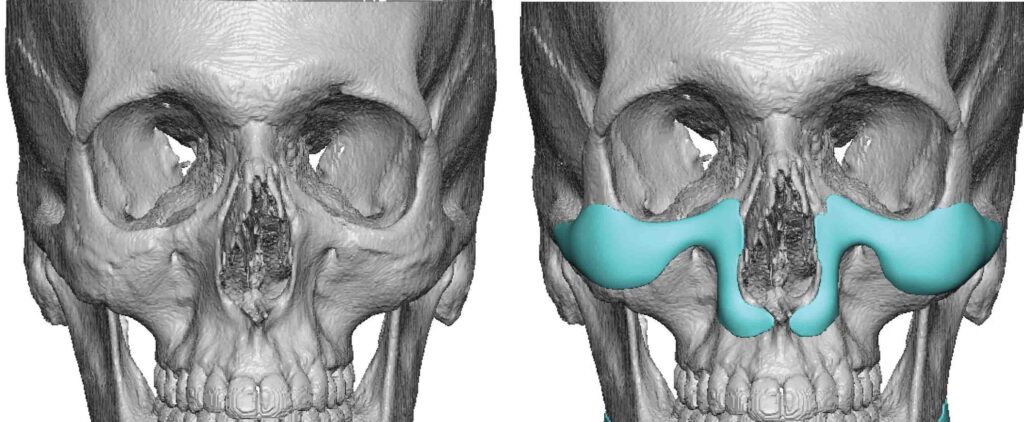

paranasals

as you can see now that some swellings gone down my nasolabials are getting more prominent again. I don't want fat grafting, i wanted to fake some bone support instead. Surgeon thinks a facelift oughtta do it, but id rather augment the structure, facelift seems like a subscription based service where ive gotta do it again and again over the years to keep fixing it.

I've seen a few different shapes, ones with a hood on each side of the nose, ones with one big hoof under the nose, and ones that trace all the way up the side if the nose and also augment the infras. This is more of a full midface augmentation. Do these look stupid in practice or no?

Should I get paranasals, and what shape would work best?

as you can see now that some swellings gone down my nasolabials are getting more prominent again. I don't want fat grafting, i wanted to fake some bone support instead. Surgeon thinks a facelift oughtta do it, but id rather augment the structure, facelift seems like a subscription based service where ive gotta do it again and again over the years to keep fixing it.

I've seen a few different shapes, ones with a hood on each side of the nose, ones with one big hoof under the nose, and ones that trace all the way up the side if the nose and also augment the infras. This is more of a full midface augmentation. Do these look stupid in practice or no?

Should I get paranasals, and what shape would work best?